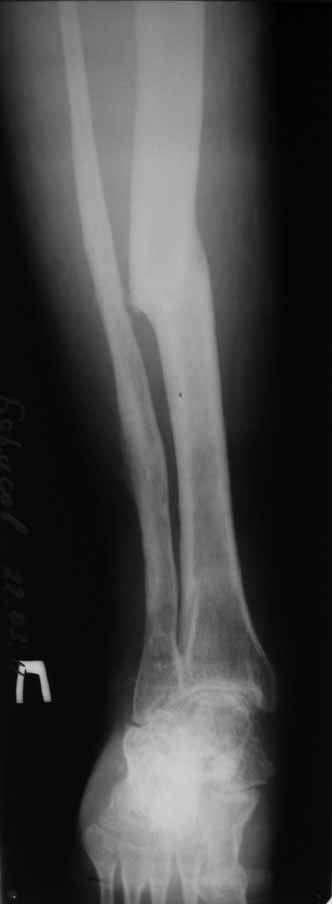

Пациент 29 лет. Неоднократно оперированная Coxa Vara.

В анамнезе этапные операции по поводу устранения Coxa Vara, формирование артродеза коленного сустава, удлинения бедра. В данный момент беспокоит укорочение 7 см, эквинус стопы. Объективно: - местный статус виден на фото, сосудистых и неврологических расстройств нет. Обратился в консультативном порядке, настроен на удлинение голени в г.Волгограде. (со слов больного - не берут без санации очага на голени). Ваши предложения? Из кулуарных соображений - а не актиномикоз ли это? Иссечение рубцов+ VAC+ Стержень с аппаратом + микрососудистый трансплантат(?)

Ваш вопрос, коллега, вполне правомерен. В советское время те из нас, кто занимался костно-гнойной инфекцией видели достаточное количество подобных несчастных, кочующих из стационара в стационар. Своеобразный госпитализм приводил к тому, что люди тратили всю свою, как правило достаточно короткую жизнь, на лечение зачастую реально неизлечимых процессов. В данном случае имеющаяся рентгенологическая картина груботрабекулярной перестройки кости, сочетающаяся с участками склероза говорит, скорее всего, о том, что вся имеющаяся картина, дополненная чудесными фотографиями,вполне укладывается в клинику гематогенного остеомиелита, которым и страдает пациент с детства. Никакие санации, к сожалению, не приведут в данном случае к излечению, так как все имеющиеся рубцы являются зоной жизни этой самой инфекции. При продолжении лечения не исключено достаточно раннее развитие амилоидоза в этом случае. Мне кажется, что оптимальным было бы определить пациента в институт протезирования и протезостроения или в то учреждение, которое в регионе выполняет данную функцию. Специалисты помогли бы определиться с уровнем ампутации, являющейся, по сути, единственным способом разорвть порочный круг и дать пациенту возможность какой-то социальной адаптации. А в плановом порядке, насколько мне известно, можно добиться неплохого финансового обеспечения под протез конечности по квоте. Другого решения здесь нет. С уважением, Андрей Волна

извините за очепятку - не берут без санации очага на бедре. Сейчас имеется отделяемое из нижнего свища с периодическим выходом секвестром в виде мелкой крошки. Движений в ТБС почти нет - есть только сгибание градусов до 10. В стопе - только качательные.